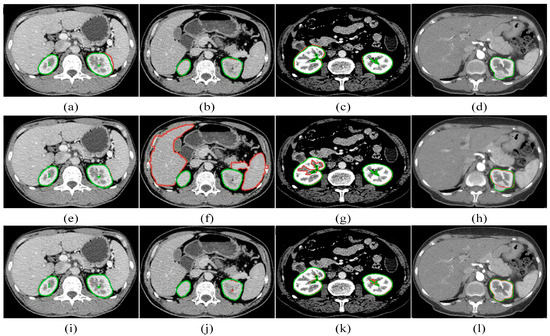

Kidney segmentation from abdominal computed tomography (CT) images is essential for computer-aided kidney diagnosis, pathology detection, and surgical planning. This paper introduces a kidney segmentation method for clinical contrast-enhanced CT images. First, it begins with shape-based preprocessing to remove the spine and ribs. [...] Read more.

Kidney segmentation from abdominal computed tomography (CT) images is essential for computer-aided kidney diagnosis, pathology detection, and surgical planning. This paper introduces a kidney segmentation method for clinical contrast-enhanced CT images. First, it begins with shape-based preprocessing to remove the spine and ribs. Second, a novel clustering algorithm and an initial kidney selection strategy are utilized to locate the initial slices and contours. Finally, an adaptive narrow-band approach based on active contours is developed, followed by a clustering postprocessing to address issues with concave parts. Experimental results demonstrate the high segmentation performance of the proposed method, achieving a Dice Similarity Coefficient of 97.4 ± 1.0% and an Average Symmetric Surface Distance of 0.5 ± 0.2 mm across twenty sequences. Notably, this method eliminates the need for manually setting initial contours and can handle intensity inhomogeneity and varying kidney shapes without extensive training or statistical modeling. Full article